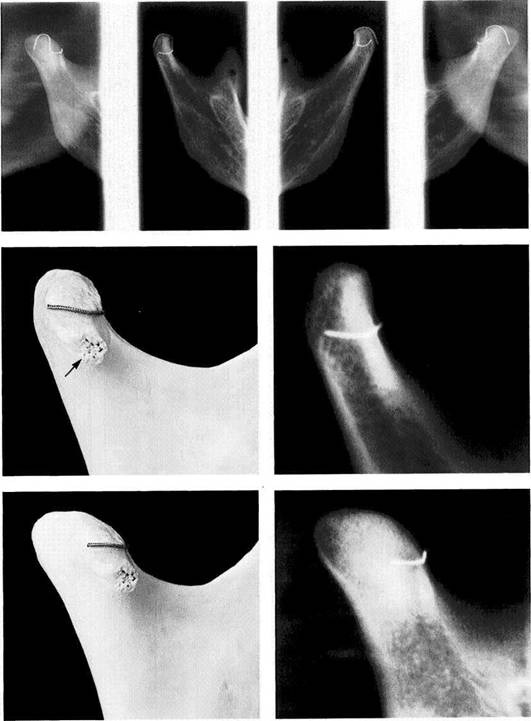

Portraying the Temporomandibular Joint with Panoramic Radiograph Machines

For several years supplementary programs that are sup­posed to allow specific views of the temporomandibular joint have been made available for panoramic radiographic machines. But in most of these programs the ascending ramus is pictured only as a segment in the same projection used for a conventional panoramic radiograph. Other pro­grams make images of the condyle from two different view­ing angles, or offer the ability to make the exposure with the jaws either closed or at maximum opening. The misleading term "functional panoramic radiograph" is sometimes used in the literature.

Fundamentally, there is no compelling medical indication for any of these modifications. In some programs the orbital movement is modified so that the condyles lie in a better position within the parabolic imaging plane, and this does produce a sharper image (Chilvarquer et al. 1988). Never­theless, in many patients this technique results in a faulty picture because the condyles tend to "wander" out of the prescribed field of the radiograph. Furthermore, considering the increased radiation dose, there is no indication for expo­sures made with the mouth both closed and open!

Biaxial radiograph of a

temporomandibular joint

specimen (from Gendex)

Biaxial radiographs of the ascend­ing rami of a macerated mandible. Exposures of the condyles were made at a 0° projection angle (inner radiographs) and at a 40° projection (outer right and left). It can be seen near the edge of the right picture that the image of the left condyle is distorted posteriorly. At this angle parts of the contour of the condyle are hidden and so cannot be evalu­ated correctly. The vertical wire marks the central sagittal plane of the condyle and the horizontal wire outlines its lateral portion.

0° projection with the

program

Left: A macerated right condyle. The wire marks the lateral bound­ary of the former fibrocartilaginous articular surface. With a 0° projec­tion the path of the rays is parallel with the long axis of the condyle. Below the wire an enlarged lateral condylar pole (arrow) can be seen.

Right: Radiograph of the same condyle. A part of the articular surface is superimposed over the condylar process.

373 40° projection with the temporomandibular joint program

Left: The same condyle as shown in Figure 372, but now in a 40° projec­tion. Here the transverse extent of the articular surface can be seen more clearly. Compared with the conventional angulation, this pro­vides a different and perhaps broader view of the joint surface. However, because it provides no information about the fibrocarti­laginous articular surface, it has no influence on treatment decisions.

of  the same

Right:   Radiograph condyle.